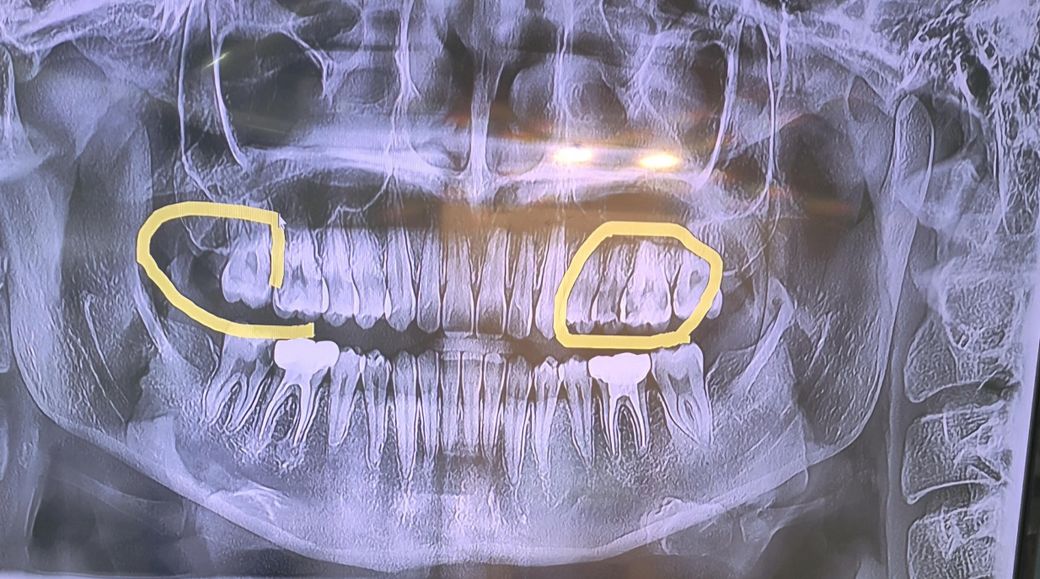

심한치통으로 치료를하러 갔는데 아픈치아 외에 저 동그라미 친 다른치아도 충치가 심해서 신경치료해야된다고 했습니다. 몇년전부터 단것만 먹으면 모든 어금니가 다 아팠는데 양치를 열심히 한뒤로 최근1년간은 단것먹어도 치통이 없어서 충치가 사라진줄 알았습니다. 저 동그라미 친부분도 충치가 심한치아라 신경 치료를 해야되는 상황인가요

?

네 엑스레이상에서 동그라미 쳐진 치아 3개에 사진상 왼쪽 아래 맨뒤 어금니 다 충치보이고 꽤 깊어 신경치료 가능성이 있는 경우로 보입니다